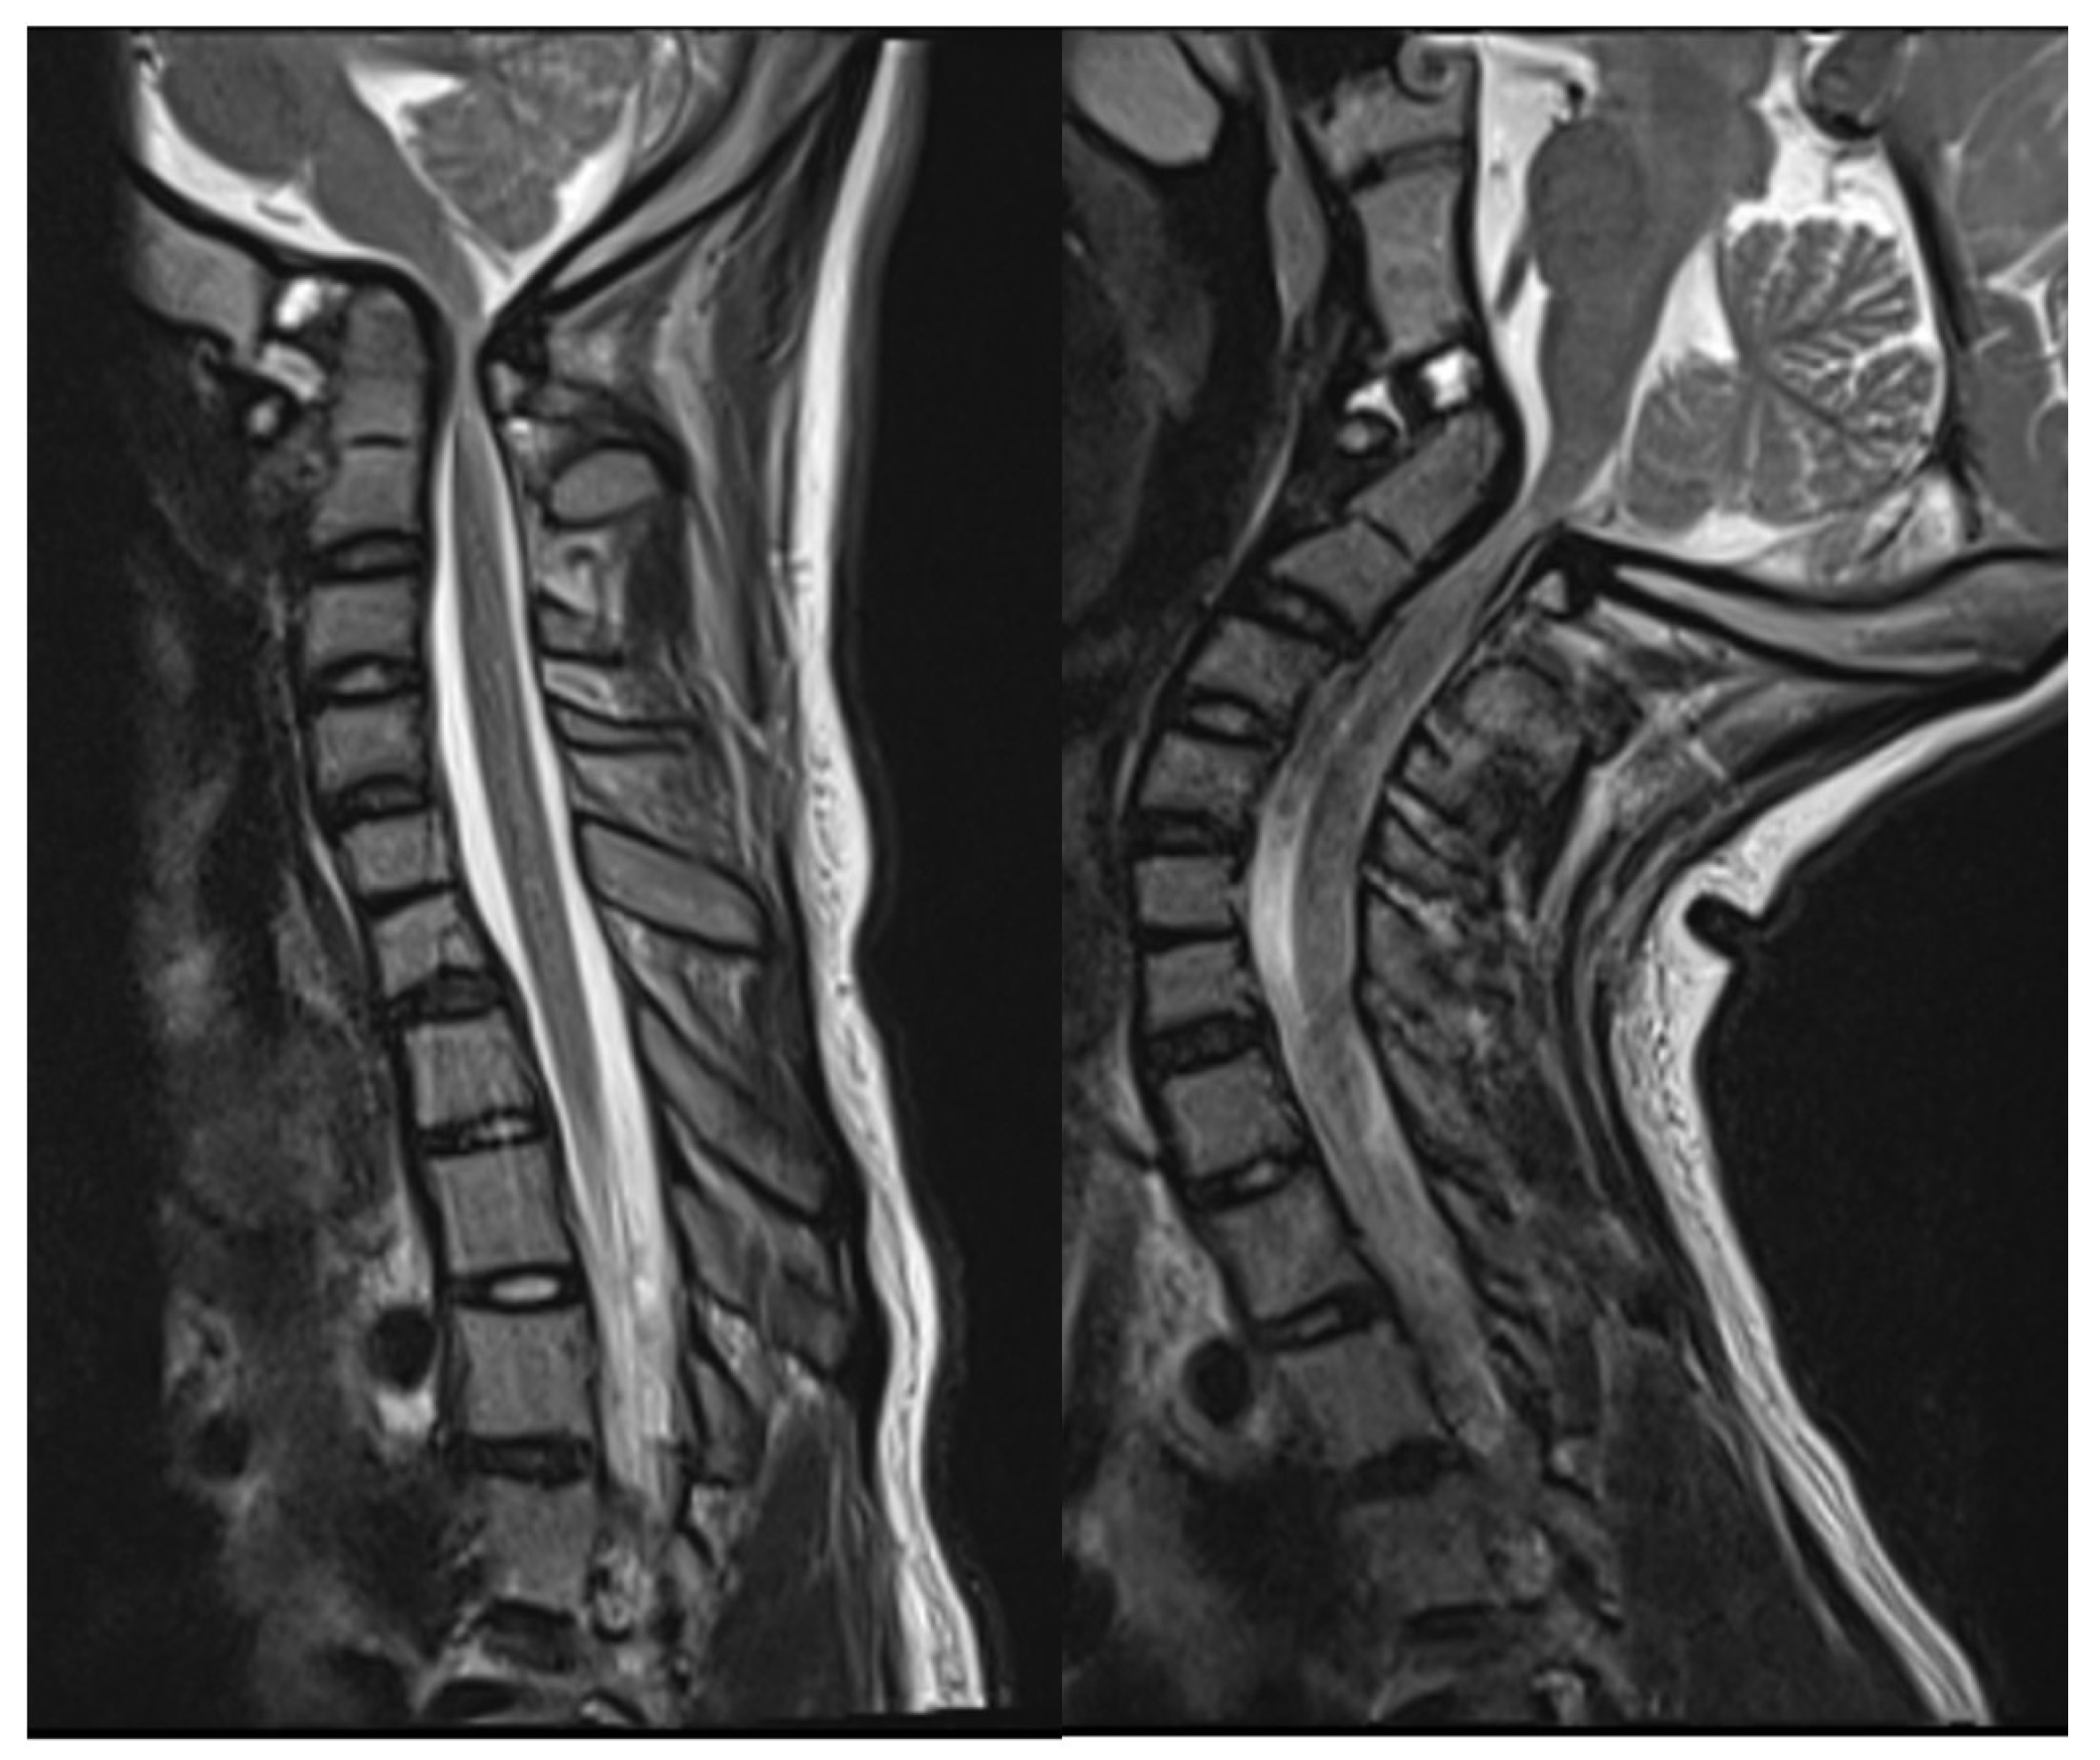

2.2. Imaging and Diagnosis